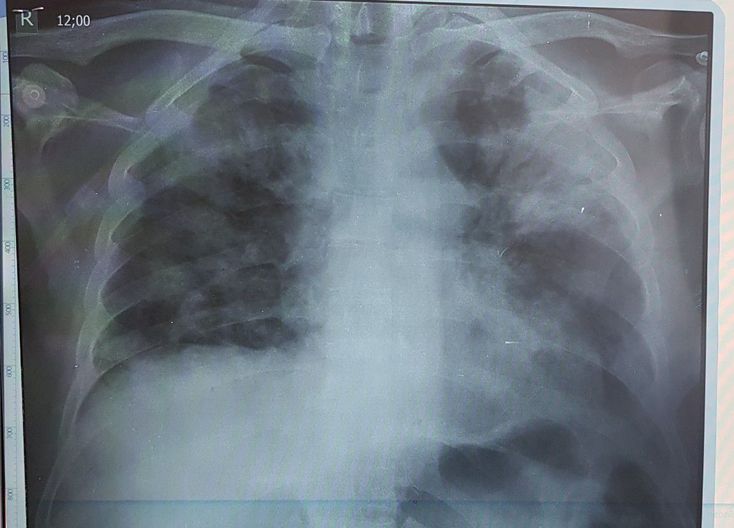

COVID-19 BEFORE TREATMENT

Infection

Lung

Coronavirus

Pneumonia

Covid 19